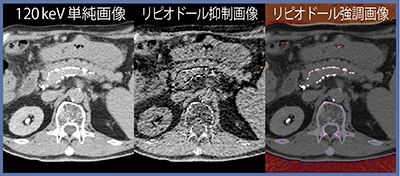

IVRでは,リピオドールのほかにヨード造影剤に混ぜたマイクロスフィア(DEB)を使うTACEも行われているため,治療効果判定でリピオドールとヨードを弁別できれば臨床的に有用である。症例3は,60歳代,男性で,HCCに対するTACEを施行した。初回のTACEではリピオドールを使用したが,2回目にはヨード造影剤を含浸したDEB-TACEを行った。DEB-TACE後CTでは,ヨード造影剤の沈着と見られる高吸収体が認められたため,DECTでリピオドールとヨード造影剤との弁別が可能か検討した結果,両者の弁別は困難であった(図3)。リピオドール,ヨード造影剤それぞれのDE係数で解析しても,両方が抑制されてしまっている。しかし,再発症例においてリピオドールの沈着により淡い造影効果が見にくくなるといったことがあるので,リピオドールとヨード造影剤の弁別は難しくはあるが臨床上重要である。

図3 症例3:HCCのTACE後のリピオドールとヨードの弁別解析

東芝メディカルシステムズのDECTは,閾値の設定を変えて,リピオドールとヨード造影剤の弁別を行うことができる。Leeらは,TACE後にリピオドールの沈着があった患者に対してDECTを施行し,肝実質,viable HCC,大動脈をcolor-coded iodine CTのウインドウ幅としてヨード造影剤の造影される範囲との閾値に設定することで,造影効果の区別が可能になったと報告した1)。当院でも同様の検討を行ったところ,閾値を設定したリピオドール抑制画像では,一部分のヨード造影剤も抑制されてしまっている(図4)。DECTでは適切な閾値の設定は必要であるが,それだけでは物質の弁別は限定的であるという結果となった。

図4 閾値を設定したリピオドールとヨード造影剤の弁別